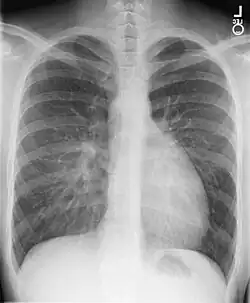

X-ray showing characteristic finding in a transposition of the great vessels, called the egg on side sign.

• Chest X-ray: On chest X-ray (CXR), transposition of the great vessels typically shows a cardio-mediastinal silhouette appearing as an "egg on a string ", in which the enlarged heart represents an egg on its side and the narrowed, atrophic thymus of the superior mediastinum represents the string.[4]